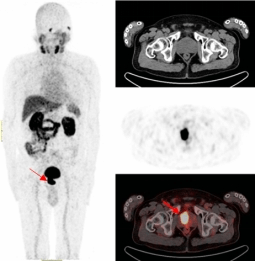

一名75的岁男性患者自2019年确诊前列腺癌后,先后接受过两次内分泌治疗及前列腺癌根治术的综合治疗。在术后两年的复查中发现血PSA持续升高,CT检查和全身骨显像检查均未发现明显异常,医生建议随诊,患者来到ok138cn太阳集团附属医院要求进一步检查。经核医学科68Ga-PSMA PET/CT检查后结果显示,双侧肩胛骨、左侧第9后肋、第2腰椎及纵隔淋巴结均已存在癌症转移。